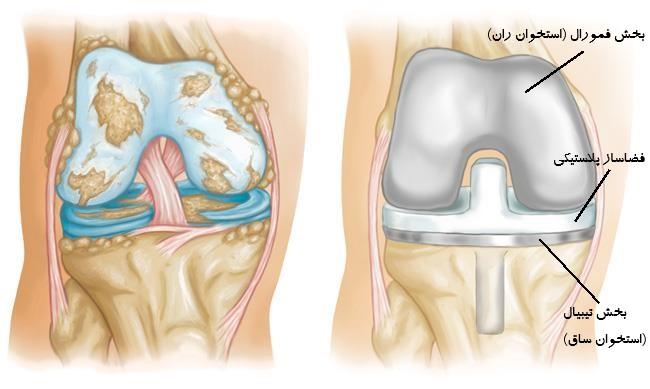

در این عمل، مفصل زانوی فرسوده و آسیبدیده با یه مفصل مصنوعی جایگزین میشه تا عملکرد زانو برگرده. اول پزشک برشی در قسمت جلوی زانو ایجاد میکنه و سر و انتهای استخوانهای ران و درشتنی رو میبره تا مفصل قدیمی زانو کاملاً دیده بشه. بعد استخوانها رو به اندازه و شکل مناسب برای اتصال به قسمتهای مصنوعی تراش میدن. سپس قسمتهای فلزی مفصل مصنوعی رو با استفاده از سیمان به استخوانها متصل میکنن تا مفصل جدید ثابت بشه. در نهایت زخم رو میدوزن و عمل تموم میشه. این عمل میتونه درد و مشکلات حرکتی ناشی از آرتروز زانو رو درمان کنه و کیفیت زندگی رو بهبود ببخشه.

عمل تعویض مفصل زانو (همچنین به عنوان جراحی پروتز زانو شناخته میشود) یک فرایند جراحی بزرگ است و نیازمند زمان و تعهد مراقبتهای پساعملی است. در طول جراحی، مفصل زانو آسیب دیده با مفصل مصنوعی جایگزین میشود. این مفصل مصنوعی شامل دو قسمت است: قسمتی که به استخوان ران اتصال مییابد (فمور) و قسمتی که به استخوان ساقه متصل میشود (تیبیا). بسته به شرایط فرد، ممکن است قسمتی از استخوان پا نیز جایگزین شود (پاتلا).

در ابتدا پزشک معالج تصمیم می گیرد که آیا بیمار به بیهوشی کامل نیاز دارد و یا به بی حسی موضع ای که در ادامه اگر نیاز به بیهوشی کامل بود بیمار توسط متخصص بیهوشی بیهوش می شود و عمل جراحی آغاز می گردد در ابتدا پزشک با ایجاد شکافی کوچک در محل مفصل زانو و با استفاده ازابزارهای خاص پزشکی که در اختیار دارد مفاصل آسیب دیده را حذف می کند و در ادامه پرتز مخصوص که همان مفصل مصنوعی است که از فلز و یا پلاستیک و یا ترکیبی از این دو جنس و یا سرامیک ساخته شده است جایگزین مفصل بیمار می گردد.